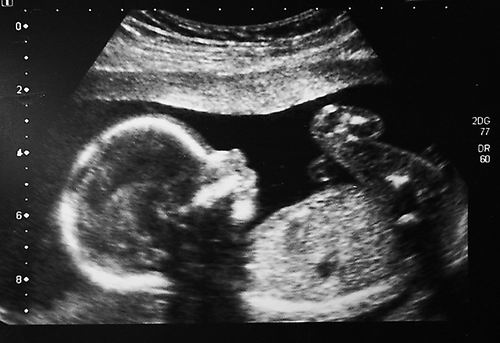

本报讯 一名两岁半的女孩成为首个在母亲子宫内接受运动神经元疾病治疗的人。如今,孩子没有表现出任何罕见的遗传病迹象。她的母亲在怀孕后期服用了一种基因靶向药物,目前孩子也在继续服药。相关研究2月19日发表于《新英格兰医学杂志》。

在研究中,这位怀孕32周的母亲每天服用Risdiplam并持续了6周。婴儿从大约1周开始服用这种药物,并可能在余生中持续服药。